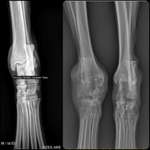

Zahnfehlstellung? / Verletzung Lefze

Ich weiß nicht, ob es vielleicht eine Zahnfehlstellung ist, aber unser Hund (15 Monate) kneift / beißt / drückt mit seinen Eckzähnen sich selbst in die Lefze von außen, we ...